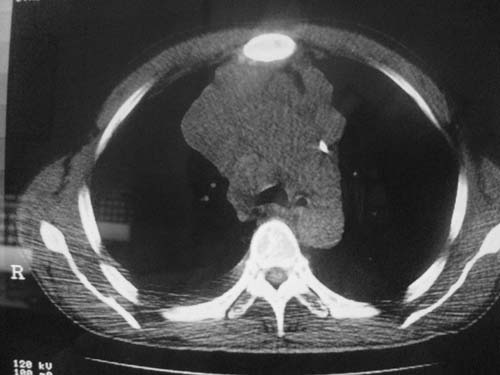

以下是引用科室第一人在2010-3-25 20:30:00的发言:[br]1:纵膈肿瘤性病变,恶性胸腺瘤可能性大伴纵膈右肺门淋巴结转移,右侧胸腔积液。[br]2:右侧肺门肿瘤性病变,纵膈淋巴结转移,右侧胸腔积液。右下叶转移。

以下是引用子期在2010-3-25 21:00:00的发言:[br]先考虑右中央型肺癌伴转移。

以下是引用江广1996在2010-3-25 22:49:00的发言:[br]通常肺癌向纵隔转移多见,纵隔肿瘤向肺内转移少见(有的表现为向肺内侵润)。本例以一元论考虑:右中心型肺癌并纵隔淋巴等多处转移。[br][br][本贴已被 江广1996 于 2010-3-25 22:50:07 修改过]

以下是引用yangyudong333在2010-3-26 6:43:00的发言:[br]“冰冻纵膈”,考虑纵膈淋巴瘤伴肺内及胸膜侵润。